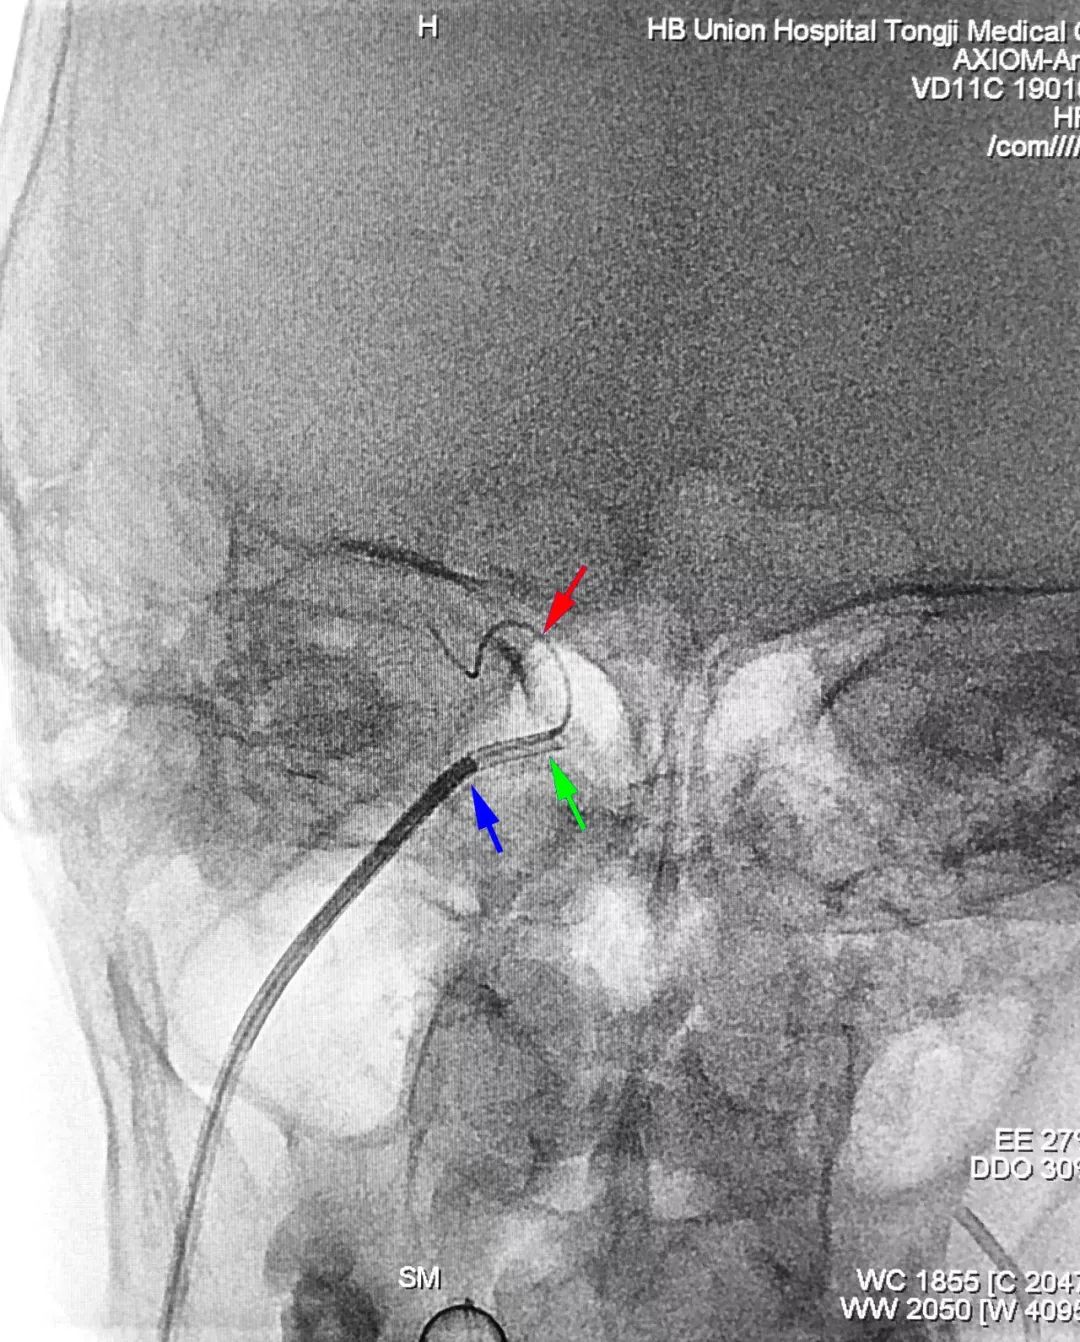

② 左颈内动脉侧位造影显示右侧岩下窦局部狭窄(左图);左颈内动脉侧位路图指示下,试图用泥鳅导丝超选右侧岩下窦,并将6F导引导管带入,但因岩下窦狭窄处阻力大,导引导管支撑力不足,管头在粗大的颈内静脉内摆动,使得泥鳅导丝无法超选入右侧岩下窦(右图);撤出泥鳅导丝,经导引导管送入Echelon-10微导管+Synchro-14微导丝,仍无法成功选入岩下窦:

③ 260 cm交换型泥鳅导丝送入6F导引导管,撤离导引导管,交换入5F单弯造影管(强生),在造影管的强劲支撑下,泥鳅导丝(红箭)成功选入右侧岩下窦;撤离造影管,同轴交换入6F导引导管(绿箭)+125 cm MPA多功能造影管(蓝箭),MPA越过岩下窦狭窄,成功将6F导引导管带入岩下窦: